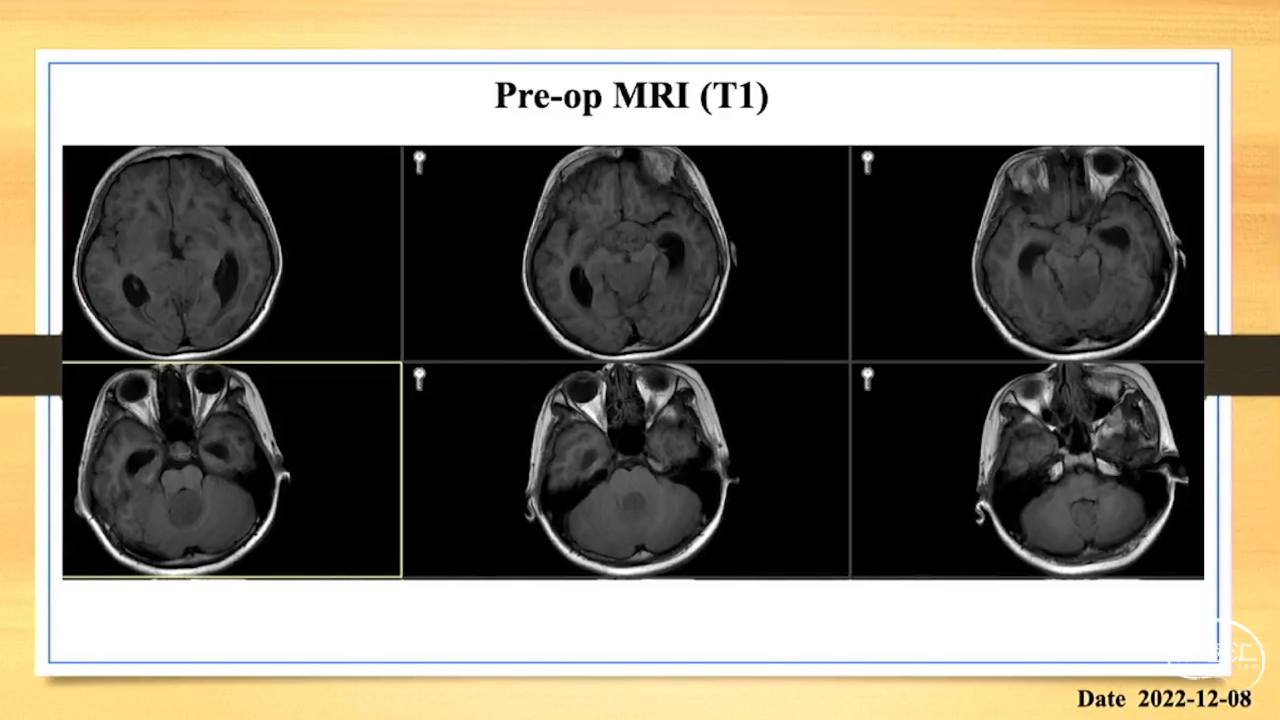

张荣教授:儿童颅内生殖细胞瘤的手术治疗

颅内生殖细胞肿瘤的治疗是手术、放疗、化疗、内分泌及其他多学科的整合治疗。及时、精准、合理的手术治疗是iGCT患者提高生存率、降低并发症、改善神经内分泌功能的关键。